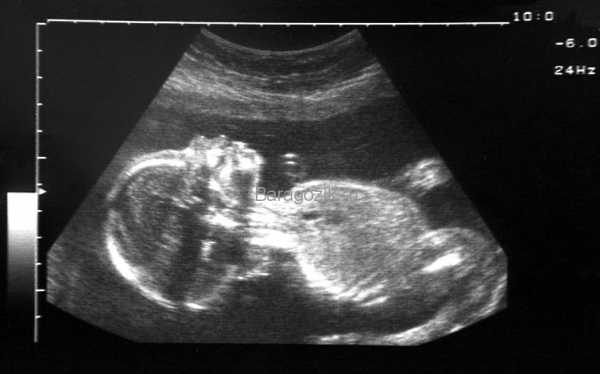

Что видно на УЗИ?

На этой неделе УЗИ считается необязательным, его назначают только в случае необходимости.

При проведении исследования большое внимание уделяется состоянию плаценты, поскольку от ее показателей зависит то, как пройдут роды. Толщина ее стенок должна равняться 24 см. С каждой неделей толщина увеличивается приблизительно на 1 см.

На мониторе мама сможет увидеть своего малыша в позе эмбриона. Его ручки скрещены на груди, ножки также скрещены и прижаты к животику, а головка опущена к груди.

УЗИ на 24 неделе беременности

На 24-й неделе УЗИ проводят только по особым показаниям или в случае, когда женщина не прошла плановое обследование раньше. Во время процедуры специалист изучает состояние органов плода, диагностирует возможные нарушения. Особое внимание уделяется сердцебиению ребенка. В норме его частота не должна превышать 180-190 ударов в минуту, иначе можно заподозрить кислородное голодание. В этом случае нужно будет провести допплеровское исследование, чтобы оценить кровоток в сосудах пуповины. Кроме того, при УЗИ хорошо просматривается плацента (ее толщина в норме – 24 мм, а степень зрелости должна быть равна нулю).

Фото УЗИ на 24 неделе беременности